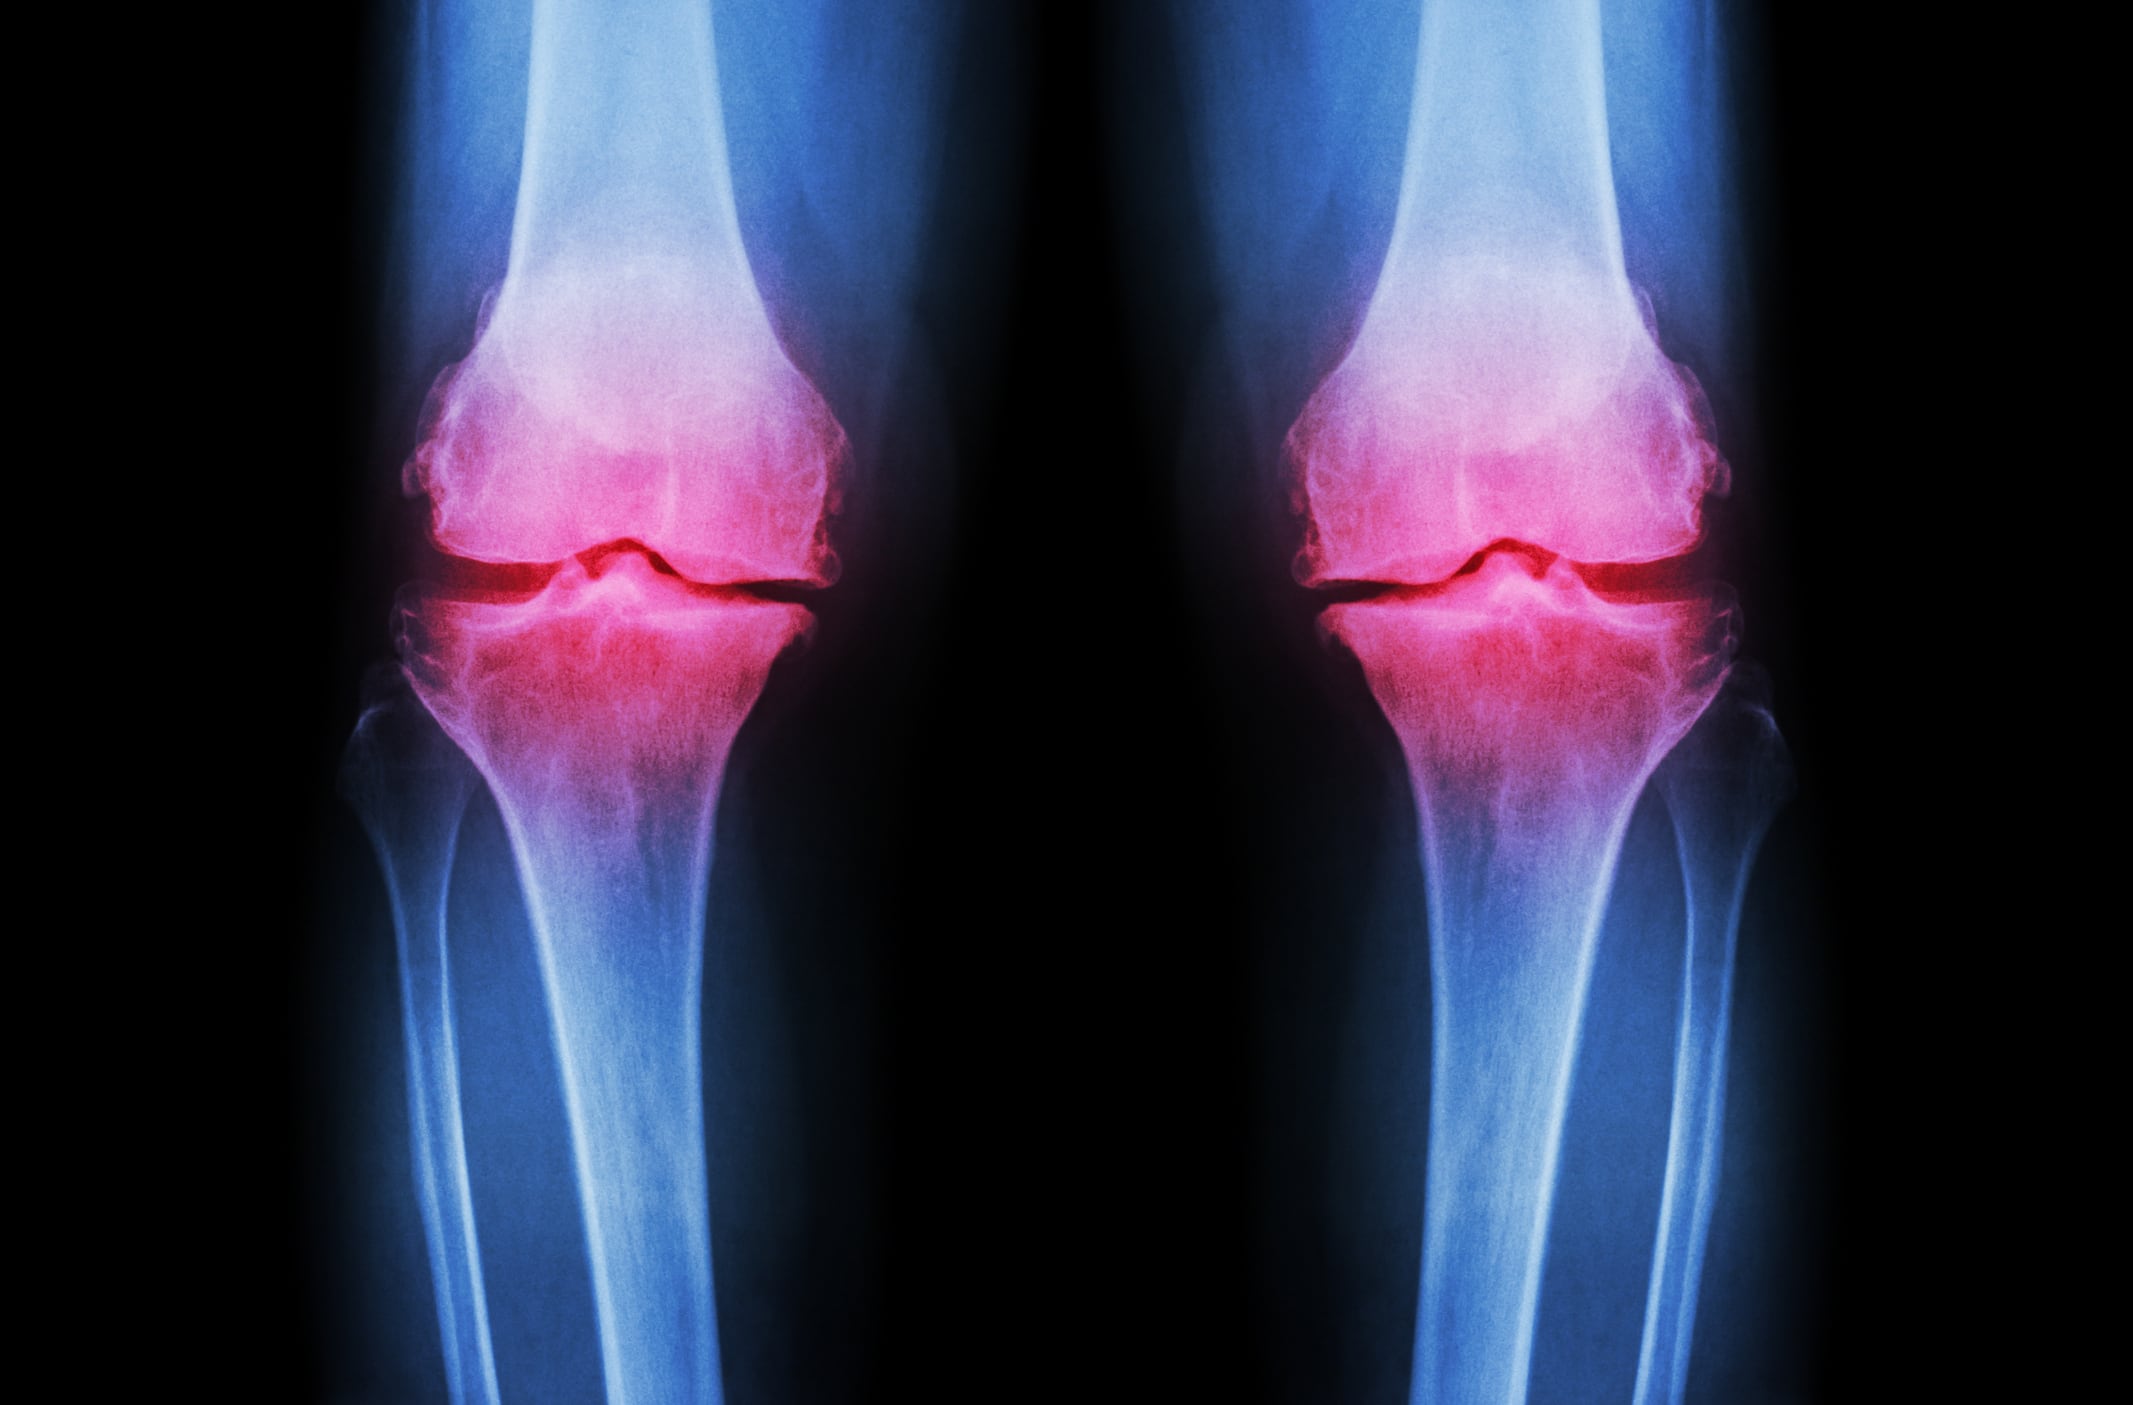

Whole-body, lumbar spine and femur BMD and BMC, as well as BMD of the cortical and trabecular compartments of the distal radius and tibia were measured, along with cortical and trabecular thickness during BDC, HDBR and recovery. Data was analysed using linear mixed models.

Results for whole-body, lumbar spine and femur aBMD and BMC, vBMD of the cortical and trabecular compartments of the distal radius and tibia, and radial and tibial cortical and trabecular thickness showed no affect from the Aox-cocktail, although the authors note a “minimal effect” on oxidative stress and inflammation parameters.

The radius average of BMD, cortical BMD and thickness decreased during HDBR, while radial trabecular thickness increased significantly, only to decrease in recovery.